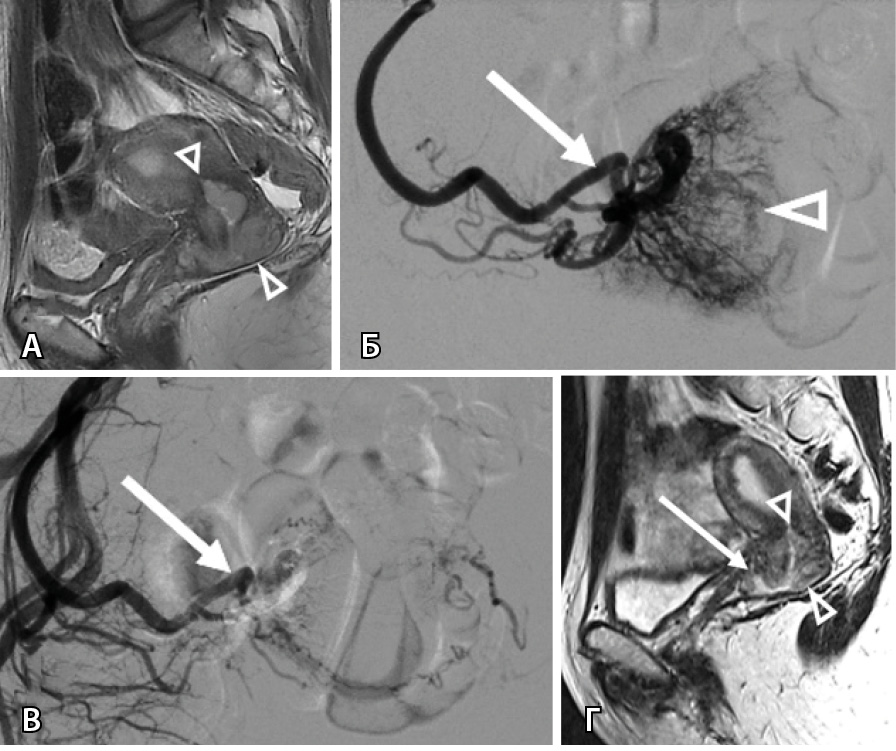

При достижении опухолью боковой стенки малого таза (7 наблюдений) отмечалась дополнительная сеть афферентов от подвздошно-поясничной артерии, которая в норме не участвует в кровоснабжении тазовых органов (рис. 3).

Рис. 3. Женщина 64 лет, рак шейки матки, рецидив через 8 месяцев после системной химиотерапии, профузное маточное кровотечение: А – магнитно-резонансная томография в сагиттальной проекции: опухоль распространяется от дна тела матки до средней трети влагалища (треугольные стрелки); Б – магнитно-резонансная томография в аксиальной проекции демонстрирует опухолевый фрагмент, достигающий боковой стенки малого таза (стрелка); В – этап трансартериальной химиоэмболизации: на ангиограмме определяется сеть опухолевых афферентов (треугольная стрелка), отходящих от подвздошно-поясничной артерии (стрелка); Г – результат эмболизации: опухолевые афференты не контрастируются, проходимость подвздошно-поясничной артерии сохранена (стрелка)